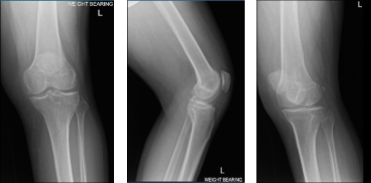

Patient presented today is male, 36 years of age. He complains his left knee is in terrible pain. He also presented his X-ray result. There are mild osteoarthritic degenerative changes but no acute fractures found. He had tried conservative management but no benefit.

MRI of Left knee